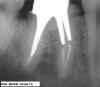

Л Ю С Я Опубликовано 25 марта, 2013 Поделиться Опубликовано 25 марта, 2013 (изменено) Сегодня собрала несколько СИЦ на работе и сделала Р-снимке:оказались все рентгеноконтрастны! Глассин-рест http://ib3.keep4u.ru/s/2013/03/25/25/2508bb9211e3063f4e91446de2d5357f.jpg Фуджи http://ib3.keep4u.ru/s/2013/03/25/60/6001b44958dd590cabe8d7e9e7968656.jpg Витремер http://ib2.keep4u.ru/s/2013/03/25/c8/c84b2541635d866bcf442cca8fa7cede.jpg аквамерон http://ib2.keep4u.ru/s/2013/03/25/b5/b5a316946eb494d7c63aa6ed9bef6964.jpg Изменено 25 марта, 2013 пользователем Л Ю С Я Ссылка на комментарий

Ico Опубликовано 25 марта, 2013 Поделиться Опубликовано 25 марта, 2013 Сегодня собрала несколько СИЦ на работе и сделала Р-снимке:оказались все рентгеноконтрастны! Глассин-рест http://ib3.keep4u.ru/s/2013/03/25/25/2508bb9211e3063f4e91446de2d5357f.jpg Фуджи http://ib3.keep4u.ru/s/2013/03/25/60/6001b44958dd590cabe8d7e9e7968656.jpg Витремер http://ib2.keep4u.ru/s/2013/03/25/c8/c84b2541635d866bcf442cca8fa7cede.jpg аквамерон http://ib2.keep4u.ru/s/2013/03/25/b5/b5a316946eb494d7c63aa6ed9bef6964.jpgЛюся.Если вы их в канал в нужном объеме заведете,выставите экспозицию в 0.8 - 0.12,то посмотрите.Я ж не с потолка так утверждаю.Кетак,Кормакс,Фуджи 1 и для преэндо еще используют "Блокаут". Ссылка на комментарий

Л Ю С Я Опубликовано 25 марта, 2013 Поделиться Опубликовано 25 марта, 2013 (изменено) Из интернета стырилВнимательно посмотрите: в 2.1 пора а в 1.1 нет. В моляре в дист ОК в мед нет. Я не думаю что в моляре в разных каналах разный сиц и поэтому рентгеноконтрастность неодинаковая Изменено 25 марта, 2013 пользователем Л Ю С Я Ссылка на комментарий